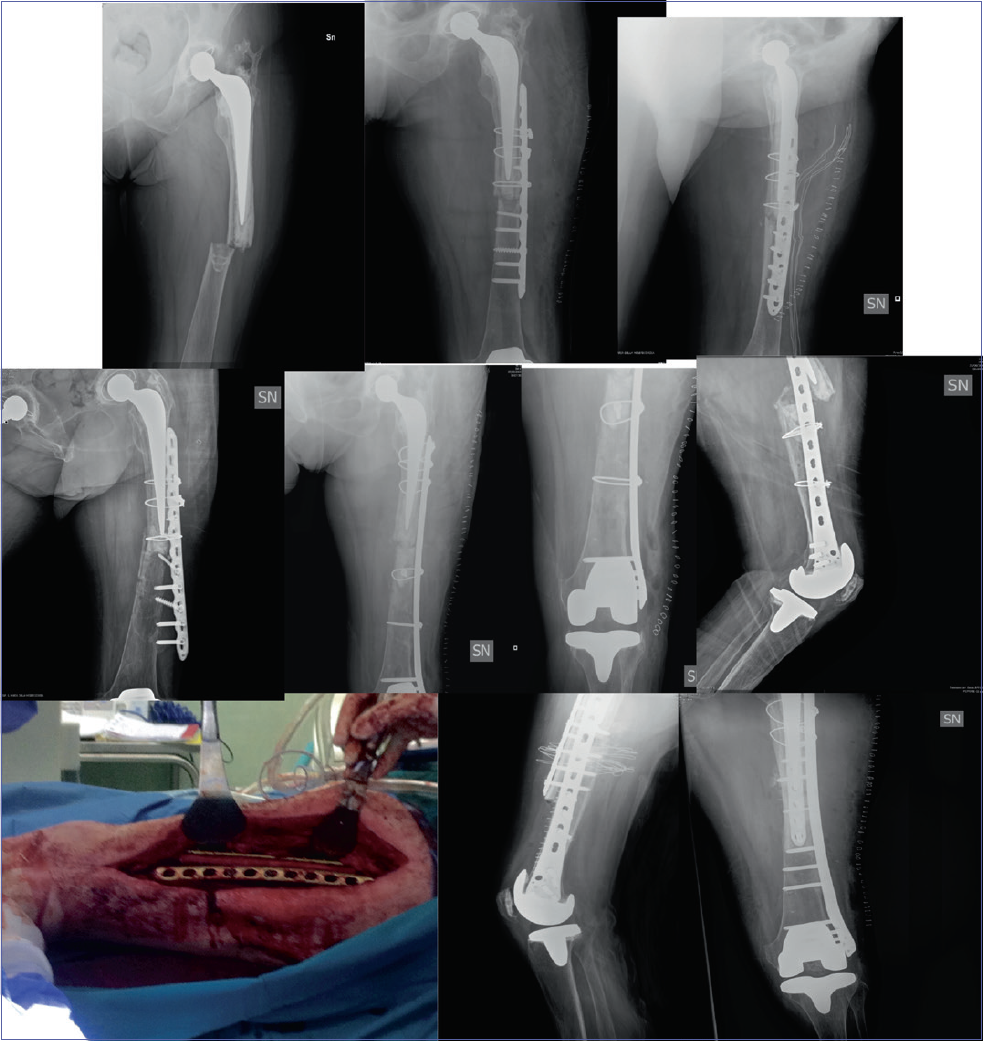

Figure 1.Surgical steps of case report.